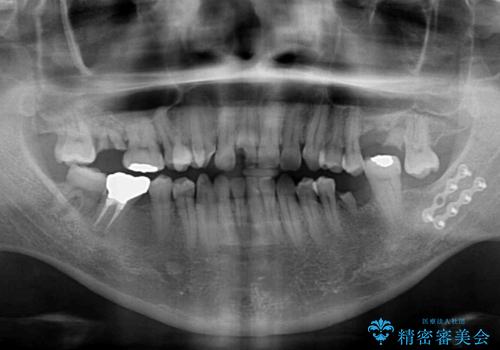

- 前歯や奥歯の虫歯を放置しており、それらの治療を契機に真っ白な歯にしたいとのことで来院された患者様です。

咬み合わせを改善するに当たって、抜歯しなければならない歯や歯列の改善が必要な箇所があったため、矯正治療やインプラント治療から始めていくこととしました。